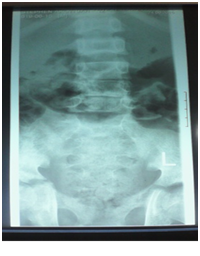

A 12-year-old boy was diagnosed with Sickle Cell Disease (SCD) with genotype SS about one year prior to. He presented with 2 months history of inability to walk and pain in both legs to Komfo Anokye Teaching Hospital in Kumasi, Ghana. The complaints were associated with marked weight loss and generalized body pain. He had been admitted about 2 weeks prior to the onset of current symptoms on account of abdominal pain and anaemia where he was haemo-transfused, given medications and subsequently discharged. There were no other significant findings in the past medical history, immunization history, nutritional and developmental histories. On examination he was found to be wasted (Weight for Height z-score <-3SD), pale, afebrile and anicteric. He had palpable axillary and inguinal lymph nodes (each measuring about 1cm to 1.5cm, mobile, non-tender and not matted). Vital signs were normal on admission. Other significant examination findings were obvious swelling of the right leg which was warm to touch, erythematous and tender on palpation. He had a gibbus deformity of the lower thoracic spine with no remarkable neurological findings in the lower limbs. A diagnosis of SCD with vaso-occlusive crises and cellulitis of the right leg was made with differential diagnosis of osteomyelitis, Deep Vein Thrombosis and Potts disease. Initial investigations revealed WBC of 13.51 X 109/dl with Neutrophils 8.83 (65.3%) Lymphocytes 4.27 (31.6%) and Monocytes 0.25(1.9%), Hemoglobin 7.1g/dl, MCV-70.7, MCH-22.4, Platelets: 538, ESR-117, INR-1.05, Prothrombin Time-14.3secs and blood sugar-6.5mmol/L. Malaria parasites were not seen on the blood smear and patient was negative for Retro-Viral Screen for HIV. Other investigations included Doppler Ultrasound, Chest X-ray, Pelvic x-ray, Thoraco-lumbo-sacral spine X-ray (Figure 1-10). Blood culture and sensitivity could not be done at the time of admission as microbiology service in the hospital had a brief logistic challenge. Radiological findings revealed the following: Reduction in the vertebral body heights of T7-T10 with associated reduction in the intervertebral disc spaces and crowding of the posterior ribs. A paravertebral soft tissue mass extending from T4 vertebral level to T11. Coarse trabeculation and sclerosis of the ribs noted. Expansion of the anterior end of the left 8th rib with ill-defined lytic areas. Buckling of the cortex of the lateral aspect of the left 9th rib, suggestive of a fracture. The imaged portion of the proximal humerus shows periarticular osteopenia. Also noted was relatively small left humeral head with left glenohumeral joint space. There are patchy homogenous opacities in both lung fields predominantly in the lower zones. There was associated silhouetting of the hemi diaphragms bilaterally and the cardiac shadow. There was generalized sclerosis of the imaged pelvic bones with coarsening of the trabeculae. The right femoral head was deformed and expanded with sclerosis and lytic areas within. There was associated narrowing of the right hip joint space. The left femoral head also showed patchy lucencies. No deformity of the left femoral head seen. The left hip joint space appeared normal. Also noted was fusion of the sacroiliac joints bilaterally. There was diffuse sclerosis of the imaged vertebrae with coarse trabeculae. The vertebral endplates of L1/L2 and L3/L4 showed sharp depression at the margins with a flat base centrally giving it the H shaped appearance. Also noted were ill-defined lytic areas in the L3 to L5 vertebrae with associated end plate irregularities and reduced intervertebral disc spaces at L3/L4 and L4/L5. No paravertebral soft tissue mass seen. No fracture or listhesis seen. Changes of the thoracic spine were described under the chest x-ray.

Figure 2 Pelvic X-ray of patient.

Figure 3 Pelvic X-ray of patient.

These radiological diagnostic features were suggestive of sickle cell disease with Thoracolumbar spondylodiscitis, likely pyogenic; Bilateral Avascular Necrosis of the femoral head (early on the left); Septic arthritis of the right hip and left shoulder joint; Osteomyelitis of the left 8th and 9th ribs. Doppler Ultrasound of the lower limb revealed the following: The right common femoral and superficial femoral veins were of normal lumen with good wall to wall compressibility, good colour doppler and spectral wave form properties. The right popliteal and posterior tibial veins however showed extensive echogenic intraluminal-filling defect with resultant loss of wall-to-wall compressibility (percentage stenosis 76%). The accompanying arteries were of normal size and caliber and showed good colour doppler and spectral properties. There was thickening of the subcutaneous tissue with dilated fluid channels seen in the right foot. Inguinal as well as popliteal lymph nodes with retention of their fatty hilum noted averaging 0.9*0.5cm. Also noted was a 1.4*0.9*1.5cm (volume about 1.0ml) anechoic collection with low-level internal echoes at the medial aspect of the proximal thigh muscles; suggestive of inflammatory changes. Based on the Doppler findings a clinical diagnosis of Right Popliteal and Posterior Tibial Vein Thrombosis with Pyomyositis in a Sickle Cell Disease patient was considered and patient was subsequently administered subcutaneous Enoxaparin 40mg daily as well as Warfarin 3mg nocte, IV Clindamycin 150mg qid, IV Ciprofloxacin. After 2 days of Warfarin and Enoxaparin, INR and PT were repeated and results were 1.1 and 15.1s respectively. The child was followed up closely for four weeks and subsequently discharge. A repeat Doppler finding revealed a completely resolved thrombus with no evidence of DVT.